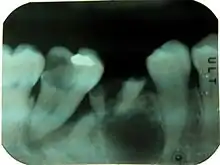

صورة شعاعية ذروية للأسنان في الجانب الأيمن من الفك السفلي، تظهر إصابة كبيرة بالتسوس في الجانب القاسي للرحى الثانية السفلية اليمنى. نفس السن أيضاَ مصاب بعيب كبير في دواعم السن. في هذه المرحلة وبدون معلومات أخرى يصعب القول ما العملية التي حدثت أولاً وأدت إلى موت اللب.